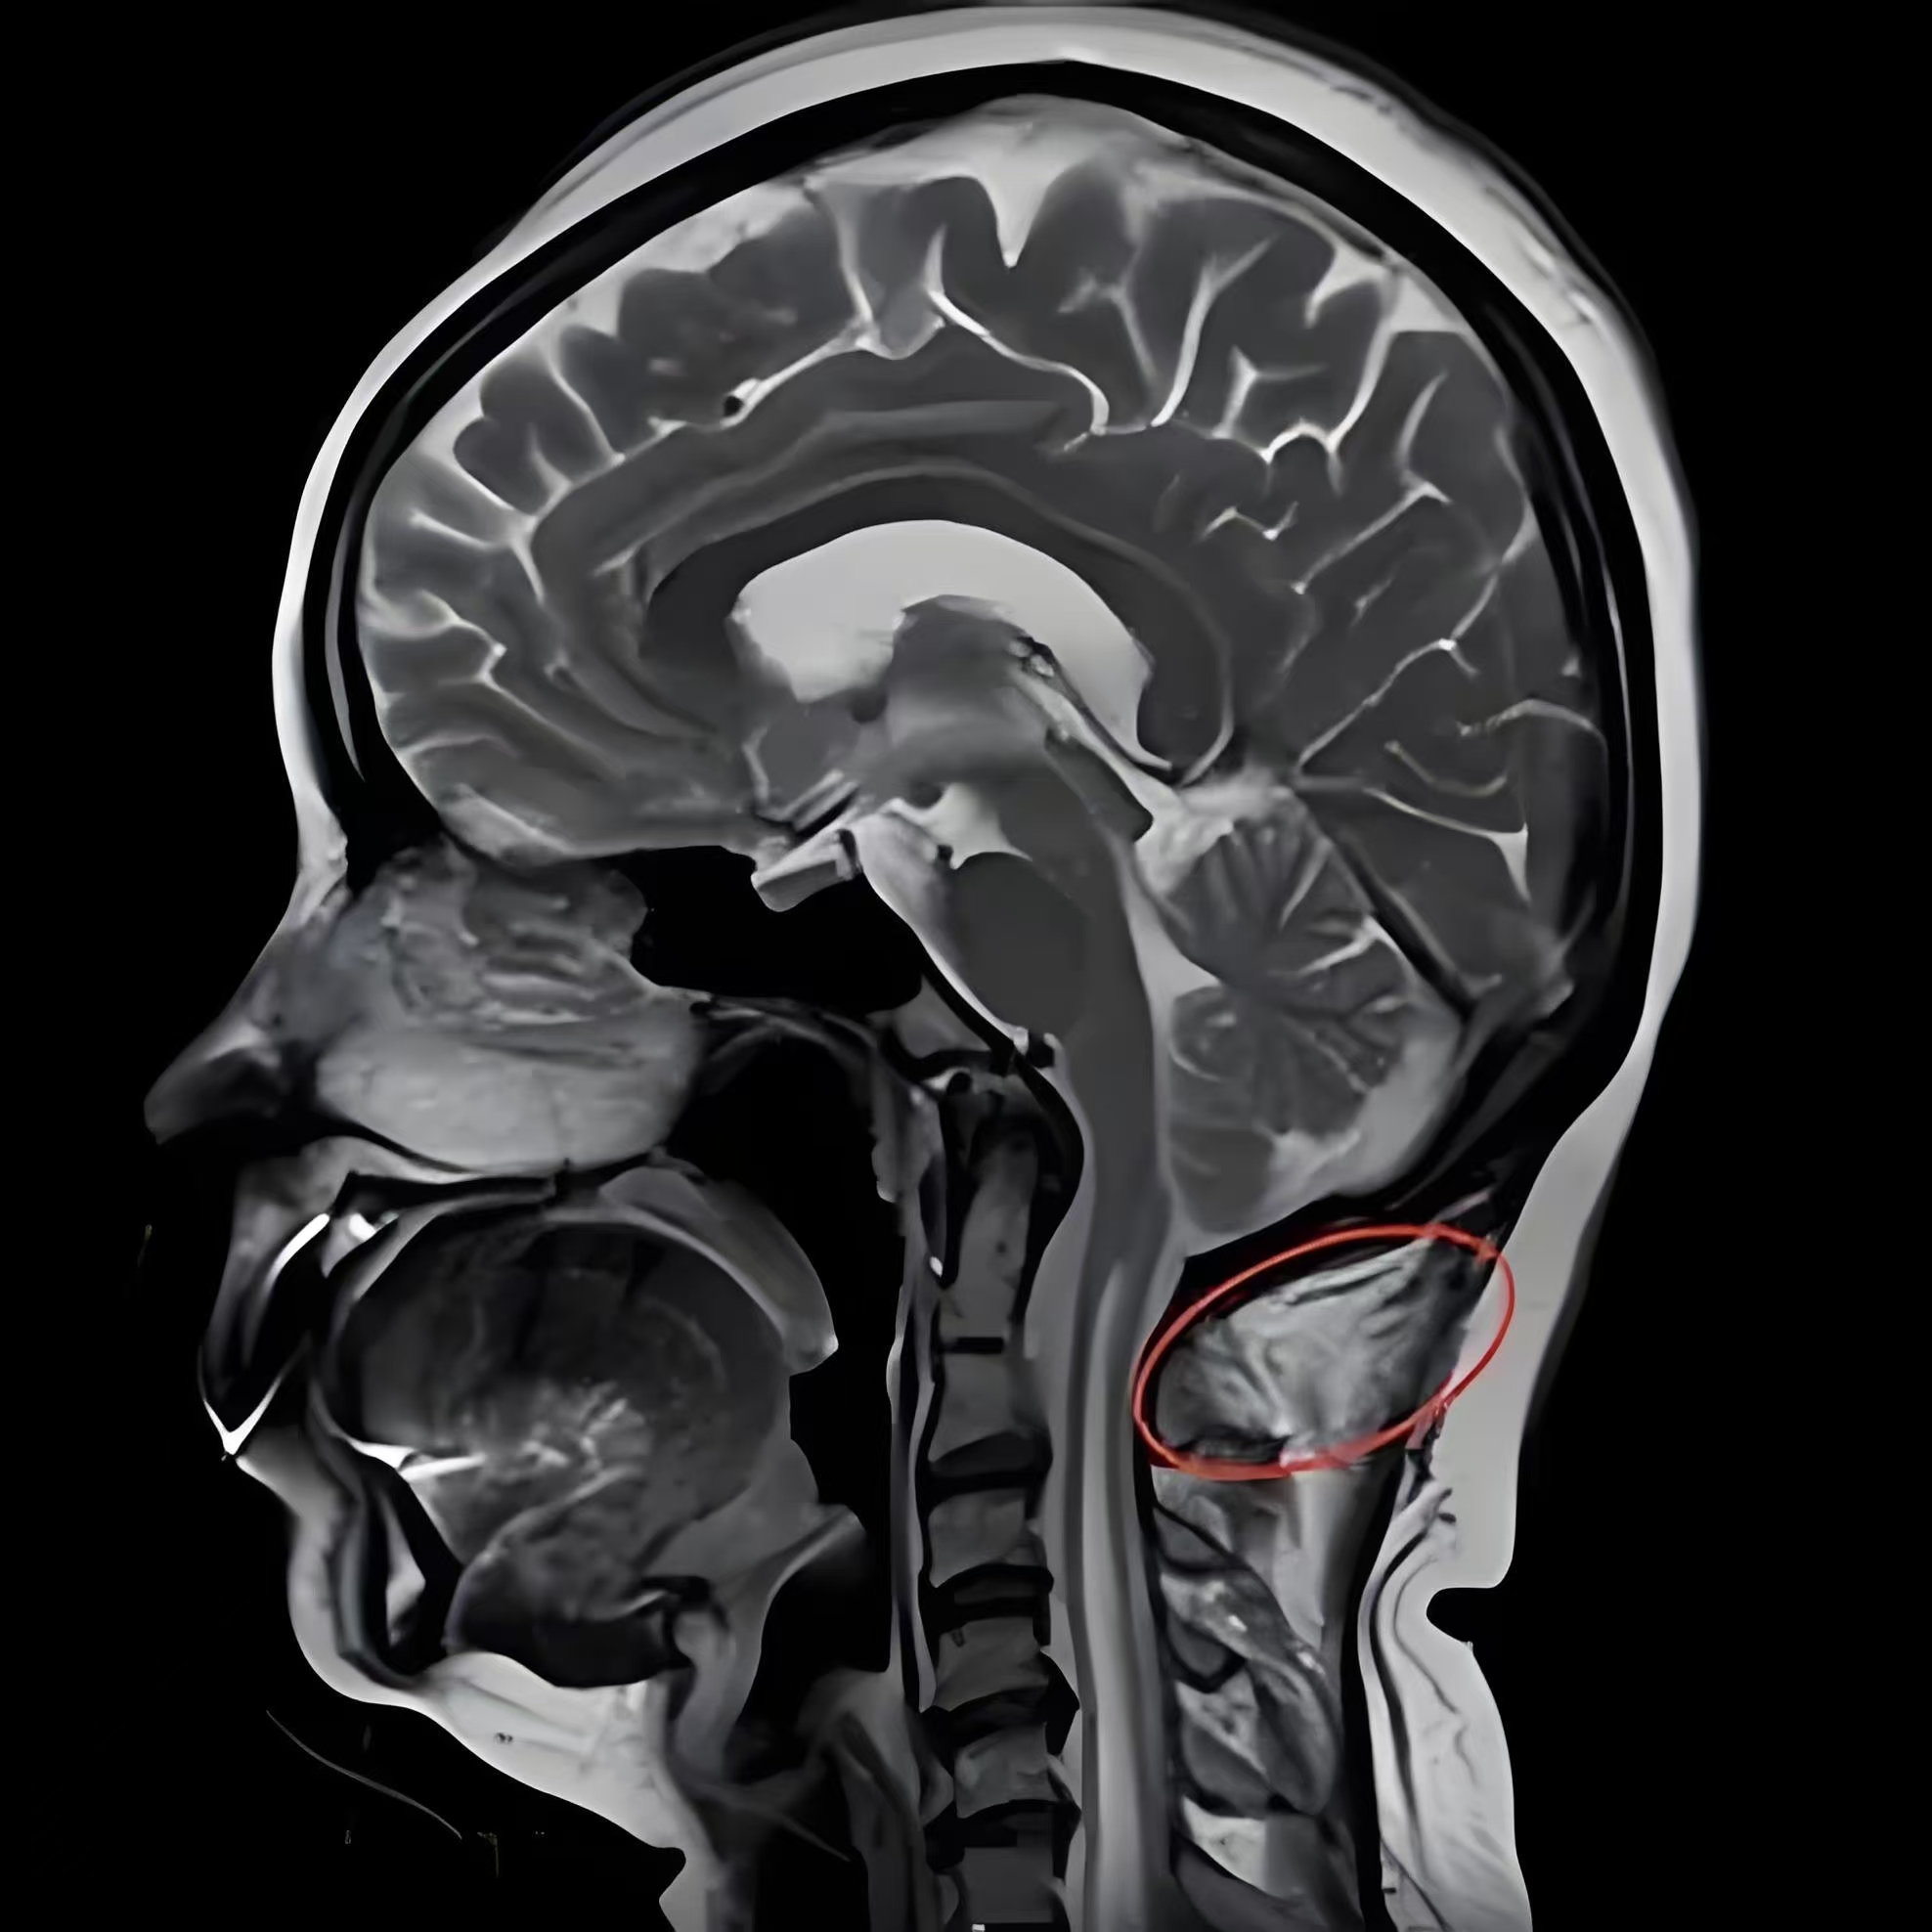

MRI是诊断本病最好的检查手段之一,尤其在矢状位可清楚的显示中脑水管,第四脑室及脑干的改变,小脑扁桃体下疝的程度及颈髓受压的情况,便于决定手术治疗方案。